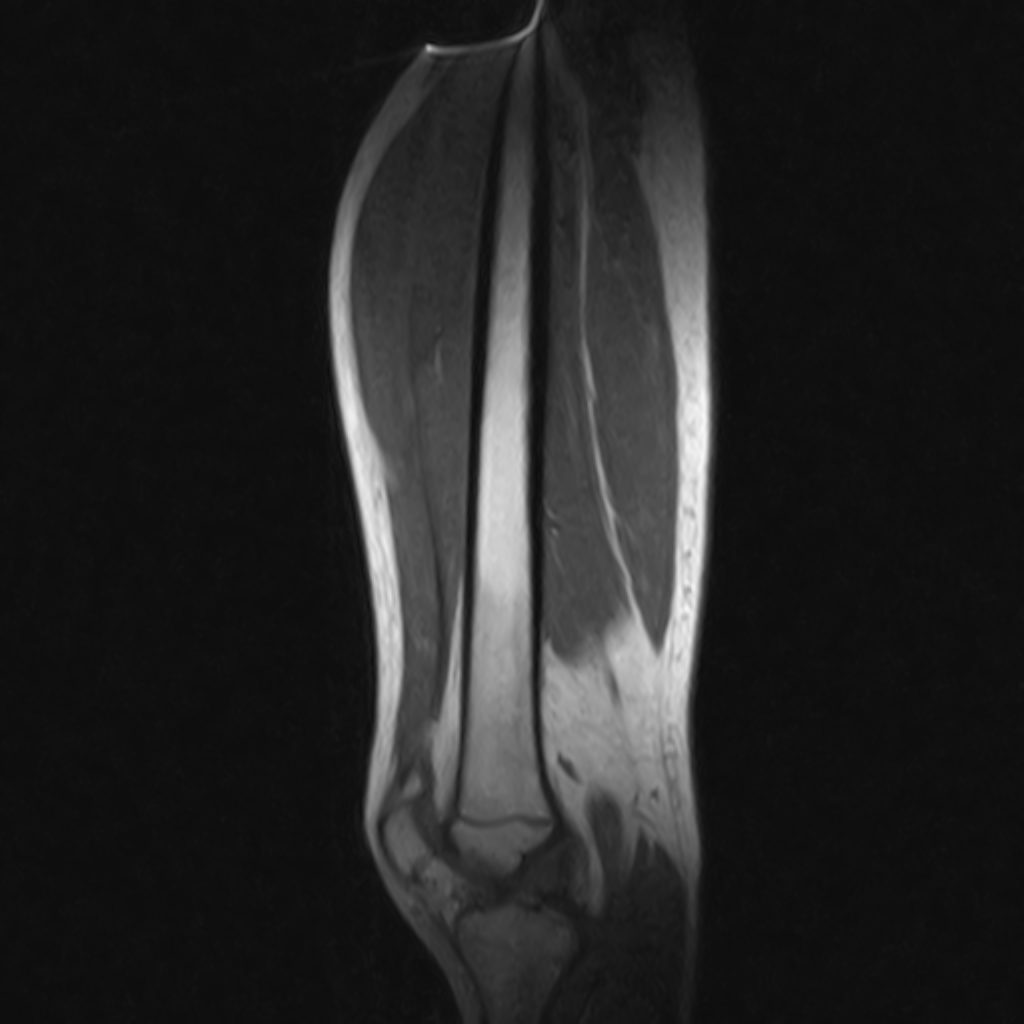

ام آر آی آتروفی عضلانی کتف بیمار

ام ار آی کتف یک روش تصویربرداری است که به وسیله آهنرباهای قدرتمند از قسمت کتف تصاویری ایجاد می کند. این نوع تصویربرداری از تشعشعات استفاده نمی کند. در این کیس آتروفی عضلانی کتف به همراه پارگی تاندون بالاخاری، بورسیت ساب دلتوئید و افیوژن مفصل دیده می شود.

– Complete tearing of supraspinatus tendon with grade 2 retraction and muscle atrophy